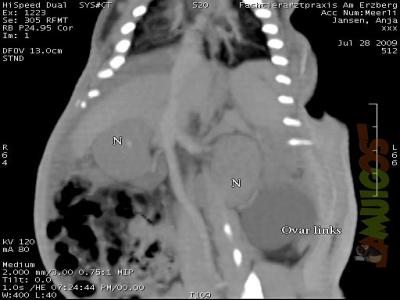

| Fotoalben > "Moderne diagnostische Methoden in der Heimtiermedizin" | ![]() |